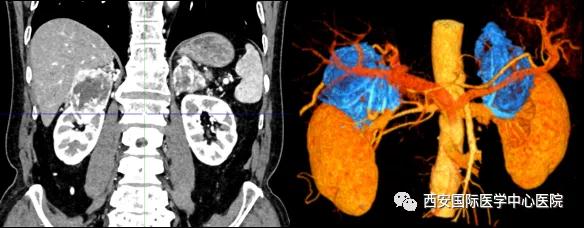

7月15日,西安國(guó)際醫(yī)學(xué)中心醫(yī)院泌尿外科楊增悅教授團(tuán)隊(duì)成功完成“機(jī)器人輔助根治性右腎、右腎上腺部分切除 左腎上腺切除 腎門淋巴結(jié)清掃術(shù)”。此臺(tái)手術(shù)涉及三個(gè)器官:右腎切除、右側(cè)腎上腺轉(zhuǎn)移瘤切除(保留部分正常腎上腺組織)、左腎上腺切除,并且清掃了腎門淋巴結(jié)。

患者一家慕名前來(lái)到西安國(guó)際醫(yī)學(xué)中心醫(yī)院找到楊增悅教授。楊增悅教授仔細(xì)看完患者的之前的影像學(xué)及病理資料后,診斷為:右腎透明細(xì)胞癌(T4N1M1);并安排他住院。而后,主管醫(yī)生及時(shí)為他完善了術(shù)前檢查及評(píng)估。7月15日,在麻醉手術(shù)中心柴偉主任、王彬榮副主任、李娟護(hù)士長(zhǎng)、李瑞剛護(hù)士長(zhǎng)及全體麻醉手術(shù)中心團(tuán)隊(duì)的有力保障下,成功完成了這臺(tái)“大”手術(shù)。

手術(shù)由楊增悅教授主持,舒濤主治醫(yī)師、王東主治醫(yī)師主刀,黃怡醫(yī)師、王平醫(yī)師協(xié)助完成。由于第四代達(dá)芬奇機(jī)器人更加靈活和精準(zhǔn)的特性,手術(shù)全程順利,尤其是完全精準(zhǔn)的“解鎖”了右腎動(dòng)脈和右腎靜脈的數(shù)十根交互纏繞的分支血管。術(shù)后患者麻醉恢復(fù)后生命體征平穩(wěn),順利返回泌尿外科普通病區(qū)進(jìn)一步康復(fù)。